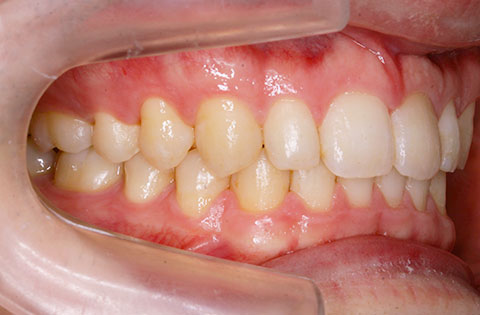

矯正前 左側

矯正後 左側